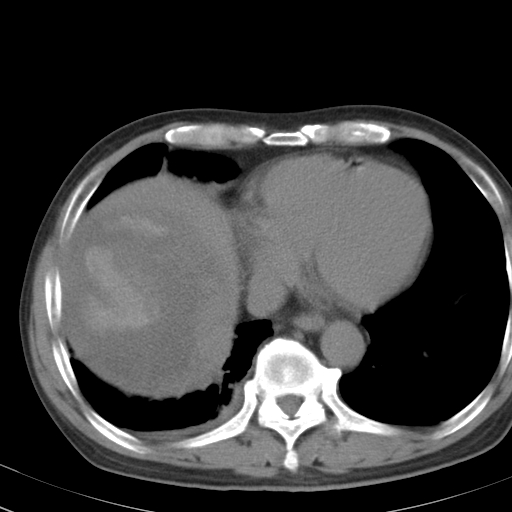

以下是引用卜一在2008-6-23 15:38:00的发言:[br]本例延时期的图象未扫完,单纯平扫 动脉期及门脉期特征分析:平扫低密度较大肿块,内见不规则出血灶,界限清楚。动脉期边缘结节样强化,门脉期病灶边缘进一步强化并范围明显缩小。因此考虑:血管瘤伴出血!

以下是引用hhcckk在2008-6-23 15:10:00的发言:[br]病灶内壁不光滑,中心高密度无强化,考虑肝癌内出血,最后两张横断面是延迟吗?病灶呈低密度。[br][br]鉴别:[br]1、脓肿,内壁光滑,不会发生出血[br]2、血管瘤,早期边缘结节样强化,可合并出血,但延迟后为等密度充填[br]